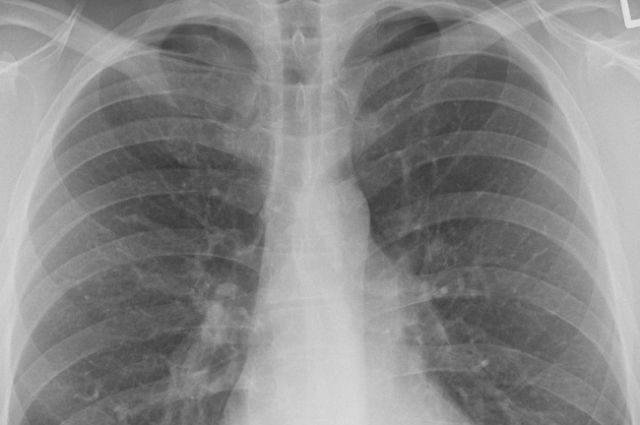

Профессор американского Университета Джорджа Мейсона, доктор биологических наук Анча Баранова рассказала, что признаками коронавируса у бессимптомных носителей могут быть сокращение объема легких и ухудшение функции почек, передает РИА Новости.

Баранова посоветовала при получении положительного результата на COVID-19 при отсутствии симптомов сделать томографию легких.